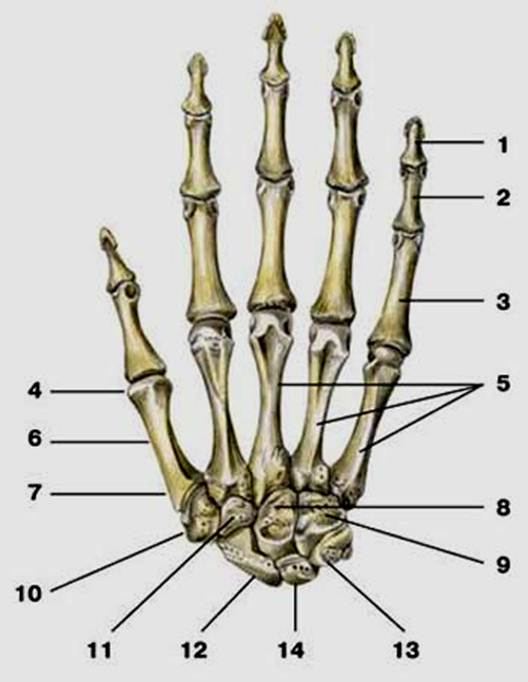

S: Числом 10 обозначена os trapezium (латинский язык).

S: Цифра 5 обозначает ossa metacarpi (латинский язык).

S: Цифрой 8 обозначена os capitatum

S: Числом 12 обозначена os scaphoideum

S: Числом 13 обозначена os triquetrum

S: Цифра 3 указывает на phalanx proximalis

S: Цифра 2 указывает на phalanx media

S: Цифра 1 указывает на phalanx distalis